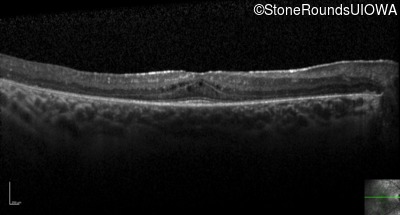

Optical Coherence Tomography - Right - 20/40 sc

Exemplar / OCT Stack

OCT Stack

Optical Coherence Tomography - Left - 20/32 -2 sc